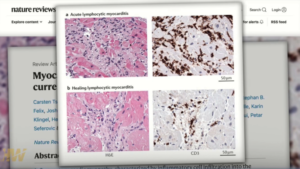

One of the many fatalities from vax-induced myocarditis (heart inflammation) came after 26-year-old Joseph Keating’s third jab on Nov. 8, 2021. The young South Dakota man died just four days after his Pfizer booster.

An autopsy confirmed the vax was responsible: “myocarditis in the left ventricle due to the recent Pfizer COVID-19 booster vaccine.” From what we know about spike protein damage to the heart (occurring disproportionately in young males), chances are that his cardiac injury began developing over the first two shots and the booster was the final straw.

“When the pathologist looked at the 22 segments of Joseph’s heart, it showed the vaccine inflamed and attacked his entire heart. There was so much damage… It was full multi-focal myocarditis, and it wasn’t just affecting one part of his heart, it was attacking his whole septum and ventricles.”

While the mainstream media works overtime to find and hype a single death from the Omicron virus, the millions of injuries and possibly hundreds of thousands of deaths from the experimental injections don’t make the news. Now and then a story that can’t be ignored—like the shots causing myocarditis in young people—is permitted in order to broadcast pharma’s spin assuring the public that it is “rare” and “mild”, two of Berry’s favorite terms to dismiss tragic outcomes.